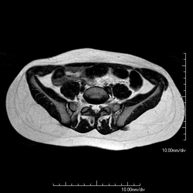

- Abdomen and pelvis

- Female pelvis MRI

This non-invasive diagnostic procedure uses an electromagnetic field and radio waves (from a transmitter and receiver) to acquire high-definition anatomical images of the pelvis. It is a radiation-free procedure. It is performed to study pathologies of the uterus, ovaries, fallopian tubes and vagina, whether they are of tumour, inflammatory or vascular origin. The procedure also enables the assessment of adjacent structures located in the pelvis, identifying any abnormalities. Sometimes intravenous contrast (gadolinium) is required to characterise the lesions.

- Male pelvis MRI

This non-invasive diagnostic procedure uses an electromagnetic field and radio waves (from a transmitter and receiver) to acquire high-definition anatomical images of the male pelvis. It is a radiation-free procedure. No prior preparation is required. In some cases, paramagnetic contrast (gadolinium) is required to characterise the lesions. This test enables the assessment of organs such as the urinary bladder, the junction between the ureters and the bladder, the prostate, the seminal vesicles, the urethra, the pelvic bones, etc.